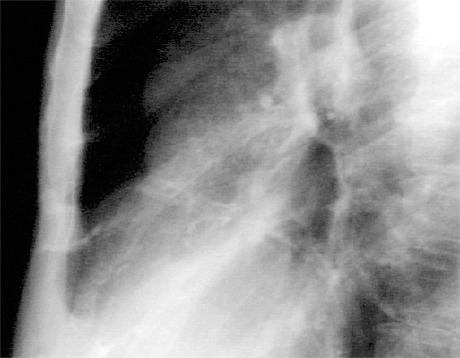

In this enlargement of the lateral view, the railroad track shadows of calcium are more easily seen. There is proximal calcification of some of the branches of the main vessel.